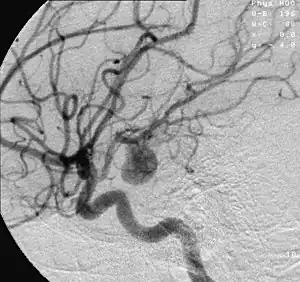

![]() | |

| Arteries beneath brain, Circle of Willis | |